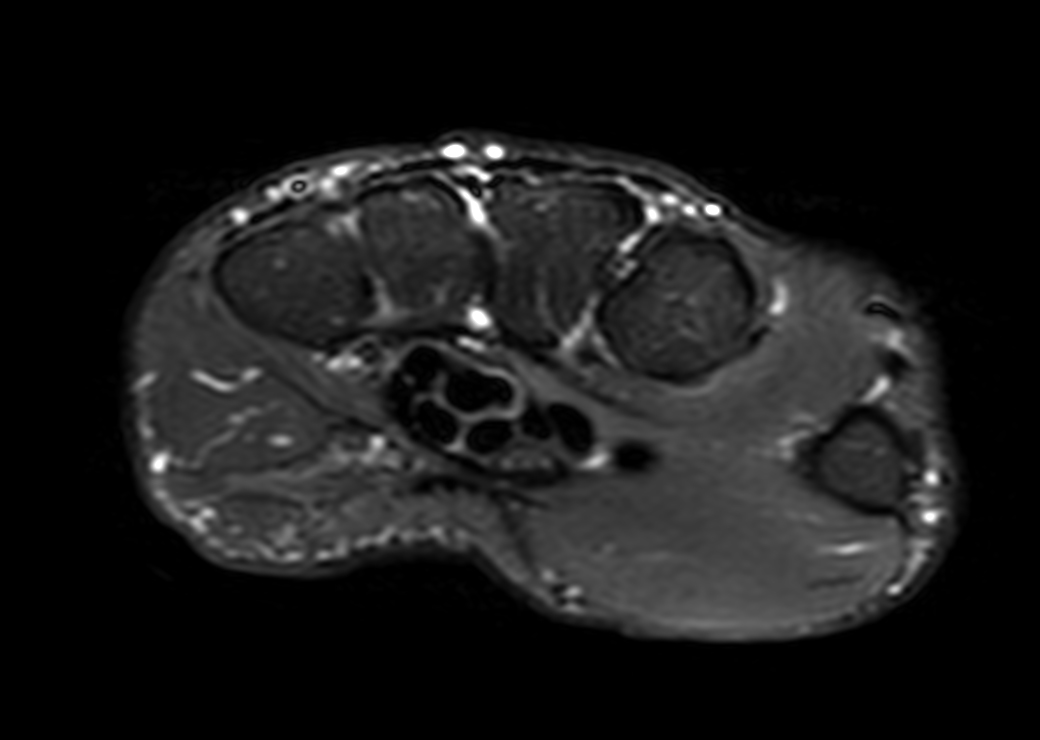

Axial T1w TSE